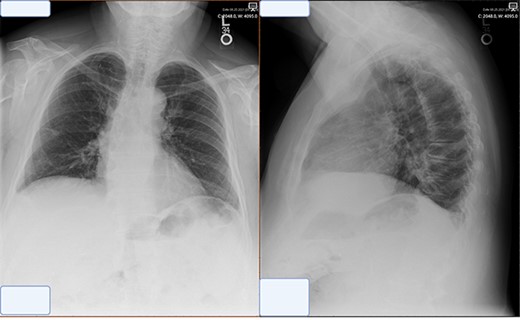

At the time of presentation to the pulmonologist, the patient was afebrile with a normal cardiopulmonary exam and vital signs. Chest X-ray revealed an enlarged right-sided heart border (Fig. 1). CT showed multiple sub-centimeter bilateral pulmonary nodules as well as a 6 x 2 cm right-sided pericardial cyst (Fig. 1). Further evaluation by MRI demonstrated gadolinium enhancement on T2 sequences with hypo enhancement noted on T1 sequences, confirming that the lesion was fluid-filled and cystic in nature.

Representative images of pericardial cysts on commonly employed imaging modalities. (A) The chest X-ray imaging of the patient described in the case report AP CXR showing widened mediastinum in a patient with a wide differential diagnosis which ultimately was found to be pericardial cyst. (B) CT imaging of the patient described in the case report with representative images of our patient demonstrating a sizeable pericardial cyst marked with red arrows and its close association with right phrenic nerve marked in gold. (C–E) MRI T1 (C) and T2 (D–E) appearances of pericardial cysts. Representative images of pericardial cyst appearance on gadolinium-enhanced MRI sequences. *Figure edited with BioRender.